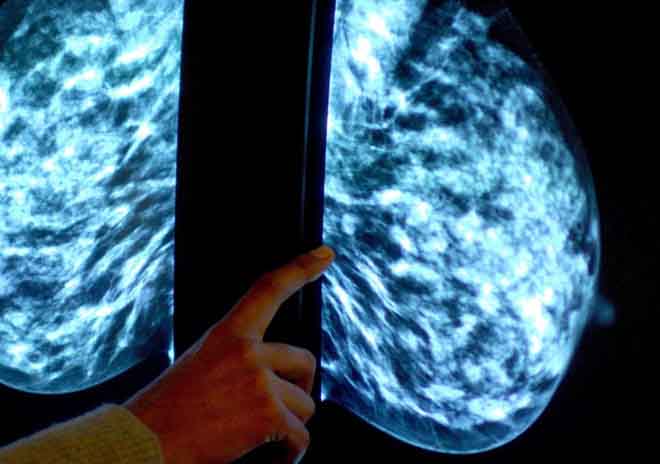

Có thể không cần hóa trị với bệnh nhân ung thư vú

Nghiên cứu bắt đầu vào năm 2006 theo dõi 10.253 phụ nữ trong độ tuổi 18-75. Bằng cách xem xét 21 dấu hiệu di truyền trong các tế bào khối u sinh thiết, xét nghiệm có thể xác định khối u hoạt động như thế nào và được đánh giá với điểm số từ 1-100 theo nguy cơ tái phát và lây lan sang cơ quan khác.

Những phụ nữ có điểm tái phát thấp nhất (dưới 10 điểm) có thể được thực hiện liệu pháp an toàn bằng cách ức chế hormone estrogen, trong khi những người có điểm số trên 26 sẽ sử dụng hóa trị để quét sạch các tế bào ung thư còn sót lại.

Tuy nhiên, trong số 9.719 bệnh nhân có thông tin theo dõi đầy đủ, 70% có điểm số từ 11-25, vùng điểm mà lợi ích của hóa trị khó được xác định và quyết định điều trị khó khăn hơn.

Họ đã phẫu thuật và xạ trị, sau đó được chỉ định ngẫu nhiên để điều trị nội tiết hoặc nội tiết cộng với hóa trị. Việc theo dõi kết quả diễn ra trong hơn 7 năm.

Kết quả cho thấy cả 2 nhóm đều tốt như nhau. Điều đó chứng tỏ hóa trị không có lợi. Sau 9 năm, 93,9% bệnh nhân trong nhóm điều trị liệu pháp nội tiết vẫn còn sống, so với con số 93,8% những người sử dụng thêm cả hóa trị.